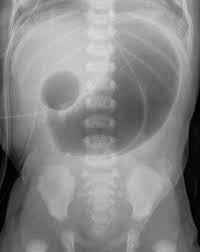

Caracterizada por un engrosamiento anormal del músculo pilórico, lo que lleva a una obstrucción de la salida gástrica. Esta condición es una causa común de vómitos no biliosos en lactantes y generalmente se presenta entre las 2 y 12 semanas de vida.

El diagnóstico se realiza principalmente mediante ecografía, que muestra un alargamiento constante y un engrosamiento de la pared del píloro, con una longitud del canal pilórico superior a 18 mm y un grosor muscular de al menos 4 mm.

Ejemplos de estenosis pilorica hipertrofica infantil.